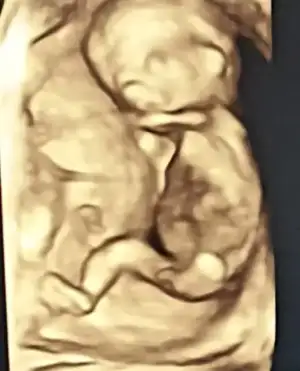

Selamlaar🌸 Bugün doktor muayenem vardı, ben de güzel haberlerle geldim🥰 Her şey iyi görünüyormuş, hareket etsin diye uğraştı biraz doktor, şükür sonunda kıpırdadı biraz. Ay görene kadar gerçekten yüreğim ağzımda bekledim, görünce gelen oh çok şükür hissi yok mu🥰 Kıza benziyor dedi bir de. Şimdi bir ay daha bekleme vakti😁

Allah allah aslında çok geç öğrenmişsiniz cinsiyeti. Ben daha 10+6 da doktor erkek dedi yani. Hatta o demeden önce eşim ekrandan farketmiş ama sormamış başka birşeydir diye 😀

Bizde fark ettik Dr kordon dedi

Eklentiler

• IMG_20220924_135521.webp

IMG_20220924_135521.webp

12,1 KB · Görüntüleme: 89